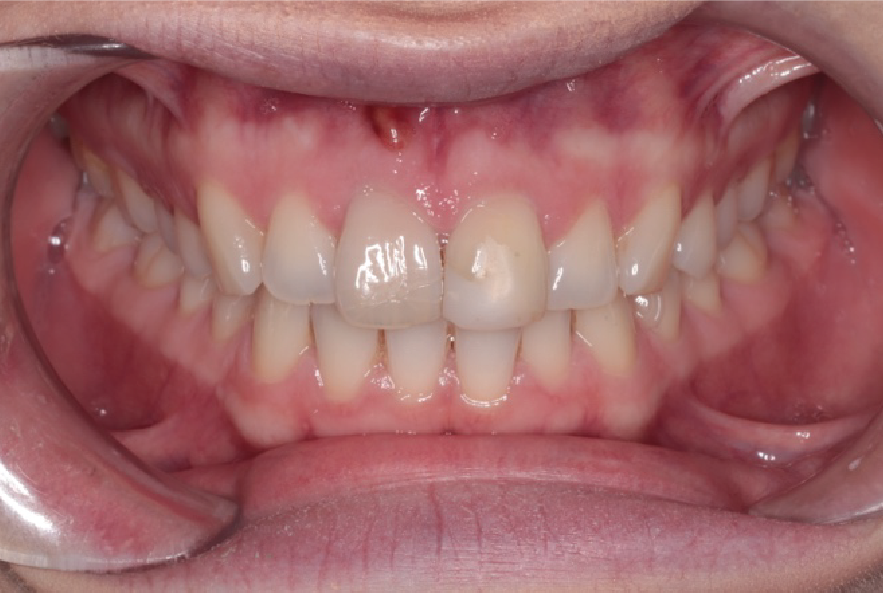

The following case presents a young lady requesting cosmetic treatment of upper central incisors. She suffered trauma to the upper incisors aged 8 and the teeth had discoloured. On examination a draining sinus and large periapical areas were associated with upper right central incisor (UR1) and upper left central incisor (UL1).

Pre-operative photo, showing sinus apical to UR1.

Right lateral showing sinus apical to UR1.